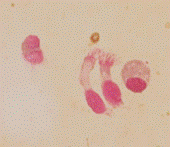

En mayo 2023 es derivado por Eo severa, deposiciones semidesligadas, síndrome febril y dolor abdominal. Como datos positivos al ingreso presenta un hemograma con anemia normocítica normocrómica, leucocitosis con neutrofilia, linfocitosis y eosinofilia severa, con plaquetas normales. Hemoglobina (Hb): 9.6 gr/dL, hematocrito (Hto): 29%, volumen corpuscular medio (VCM): 76 fl, CHCM: 35 gr/dL, glóbulos blancos (Gb): 40.800/mm3, neutrófilos segmentados (Ne): 30%, eosinófilos (Eos): 50%, recuento absoluto de eosinófilos (RAE): 20.400/mm3, linfocitos (Li): 20%, plaquetas 250.000/mm3. En el frotis los eosinófilos presentaban núcleos polilobulados y vacuolas en su interior. Eritrosedimentación (ERS): 100 mm. PCR 129 mg/L. Serología positiva para Toxocara canis. IgE dentro de límites normales. Se realiza seguimiento y controles con Infectología, descartándose cuadro de síndrome de larva migrans. Panel inmunohematológico negativo. Se solicita estudio de exoma para pesquisa de inmunodeficiencias. Resultado pendiente.

Punción aspirativa de médula ósea (PAMO) Serie megacariocítica presente, celularidad conservada. Serie eritroide: 26%, mieloide: 63%, linfoide: 11%. Citometría de flujo (CF): sin blastos. Eosinófilos: 67.1%. Estudio genético: negativo para mutaciones asociadas a eosinofilia. Estudio citogenético 46XY.